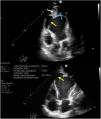

Cardiogenic shock due to a large apical pseudoaneurysm of the left ventricle: A rare complication